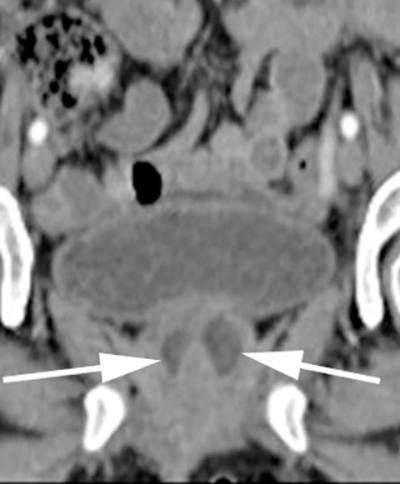

With CT imaging, diverticula appear as hypointense periurethral cystic lesions, with wall thickening and enhancement [2]. They are usually identified at the level of the pubic symphysis (Figure 2). Using voiding CT urethrography, the diverticula may opacify upon post voiding imaging [2]. To a limited extent CT can characterise urethral abnormalities [2]. It can also identify associated complicating urethral calculi and gas within the diverticula and allows for regional staging of any urethral neoplasms [2]. The disadvantage of CT is the use of ionising radiation and it is rather insensitive for small diverticula [4]. Figure 2 demonstrates a urethral diverticulum on CT imaging. Note the low attenuation, thick walled cystic density structure around the urethra measuring 2.7 x 2.0cm.

Figure 2b: Coronal CT showing urethral diverticulum (arrows).